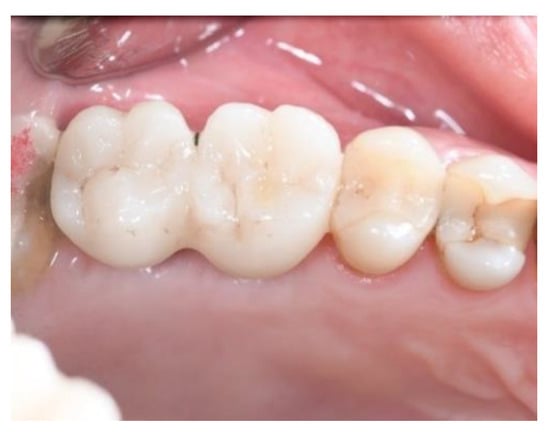

Long-Term Outcomes of Implants Placed in Maxillary Sinus Floor Augmentation with Porous Fluorohydroxyapatite (Algipore® FRIOS®) in Comparison with Anorganic Bovine Bone (Bio-Oss®) and Platelet Rich Plasma (PRP): A Retrospective Study

3. Results